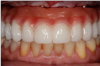

Fig 4. An 87-year-old female with mini-implants.

Figure 4

Fig 5. The patient’s decisions were based on her socioeconomic situation 10 years prior.

Figure 5

Patients seeking more comfort, better retention, and confidence from implant-retained complete dentures may choose narrow-diameter dental implants in the mandibular arch, primarily making this decision based on the lower fees for mini-implant services.15 Figure 4 and Figure 5 depict a common scenario of a maxillary complete denture opposing an implant-supported (mini-implant) complete denture. Ten years prior, the patient chose to have her mandibular arch treated with narrow-diameter implants and a mandibular removable overdenture. Figure 5 shows significant bone loss and soft-tissue recession around the narrow-diameter implants. The mini-implants serviced the patient well for 10 years but left her with a greater challenge and cost to restore the mini-implants with a new prosthesis. The dentist needed to re-engineer a means for retention other than the current ball and o-ring attachments. Over time the overdenture housings and o-ring assembly created a deformation of the ball shape of the mini-implants, decreasing the retentive nature of the o-ring and ball attachment properties. Ten years of mastication and metal-on-metal lateral movement contributed to this deformation. At 87 years old, this patient did not want to undergo additional surgical implant therapies and was looking for an alternative. The mini-implants still were able to service her. An alternative treatment option requires a cast or a milled retention bar to splint the remaining implants and development of a removable overdenture that will be retained by prefabricated attachments.